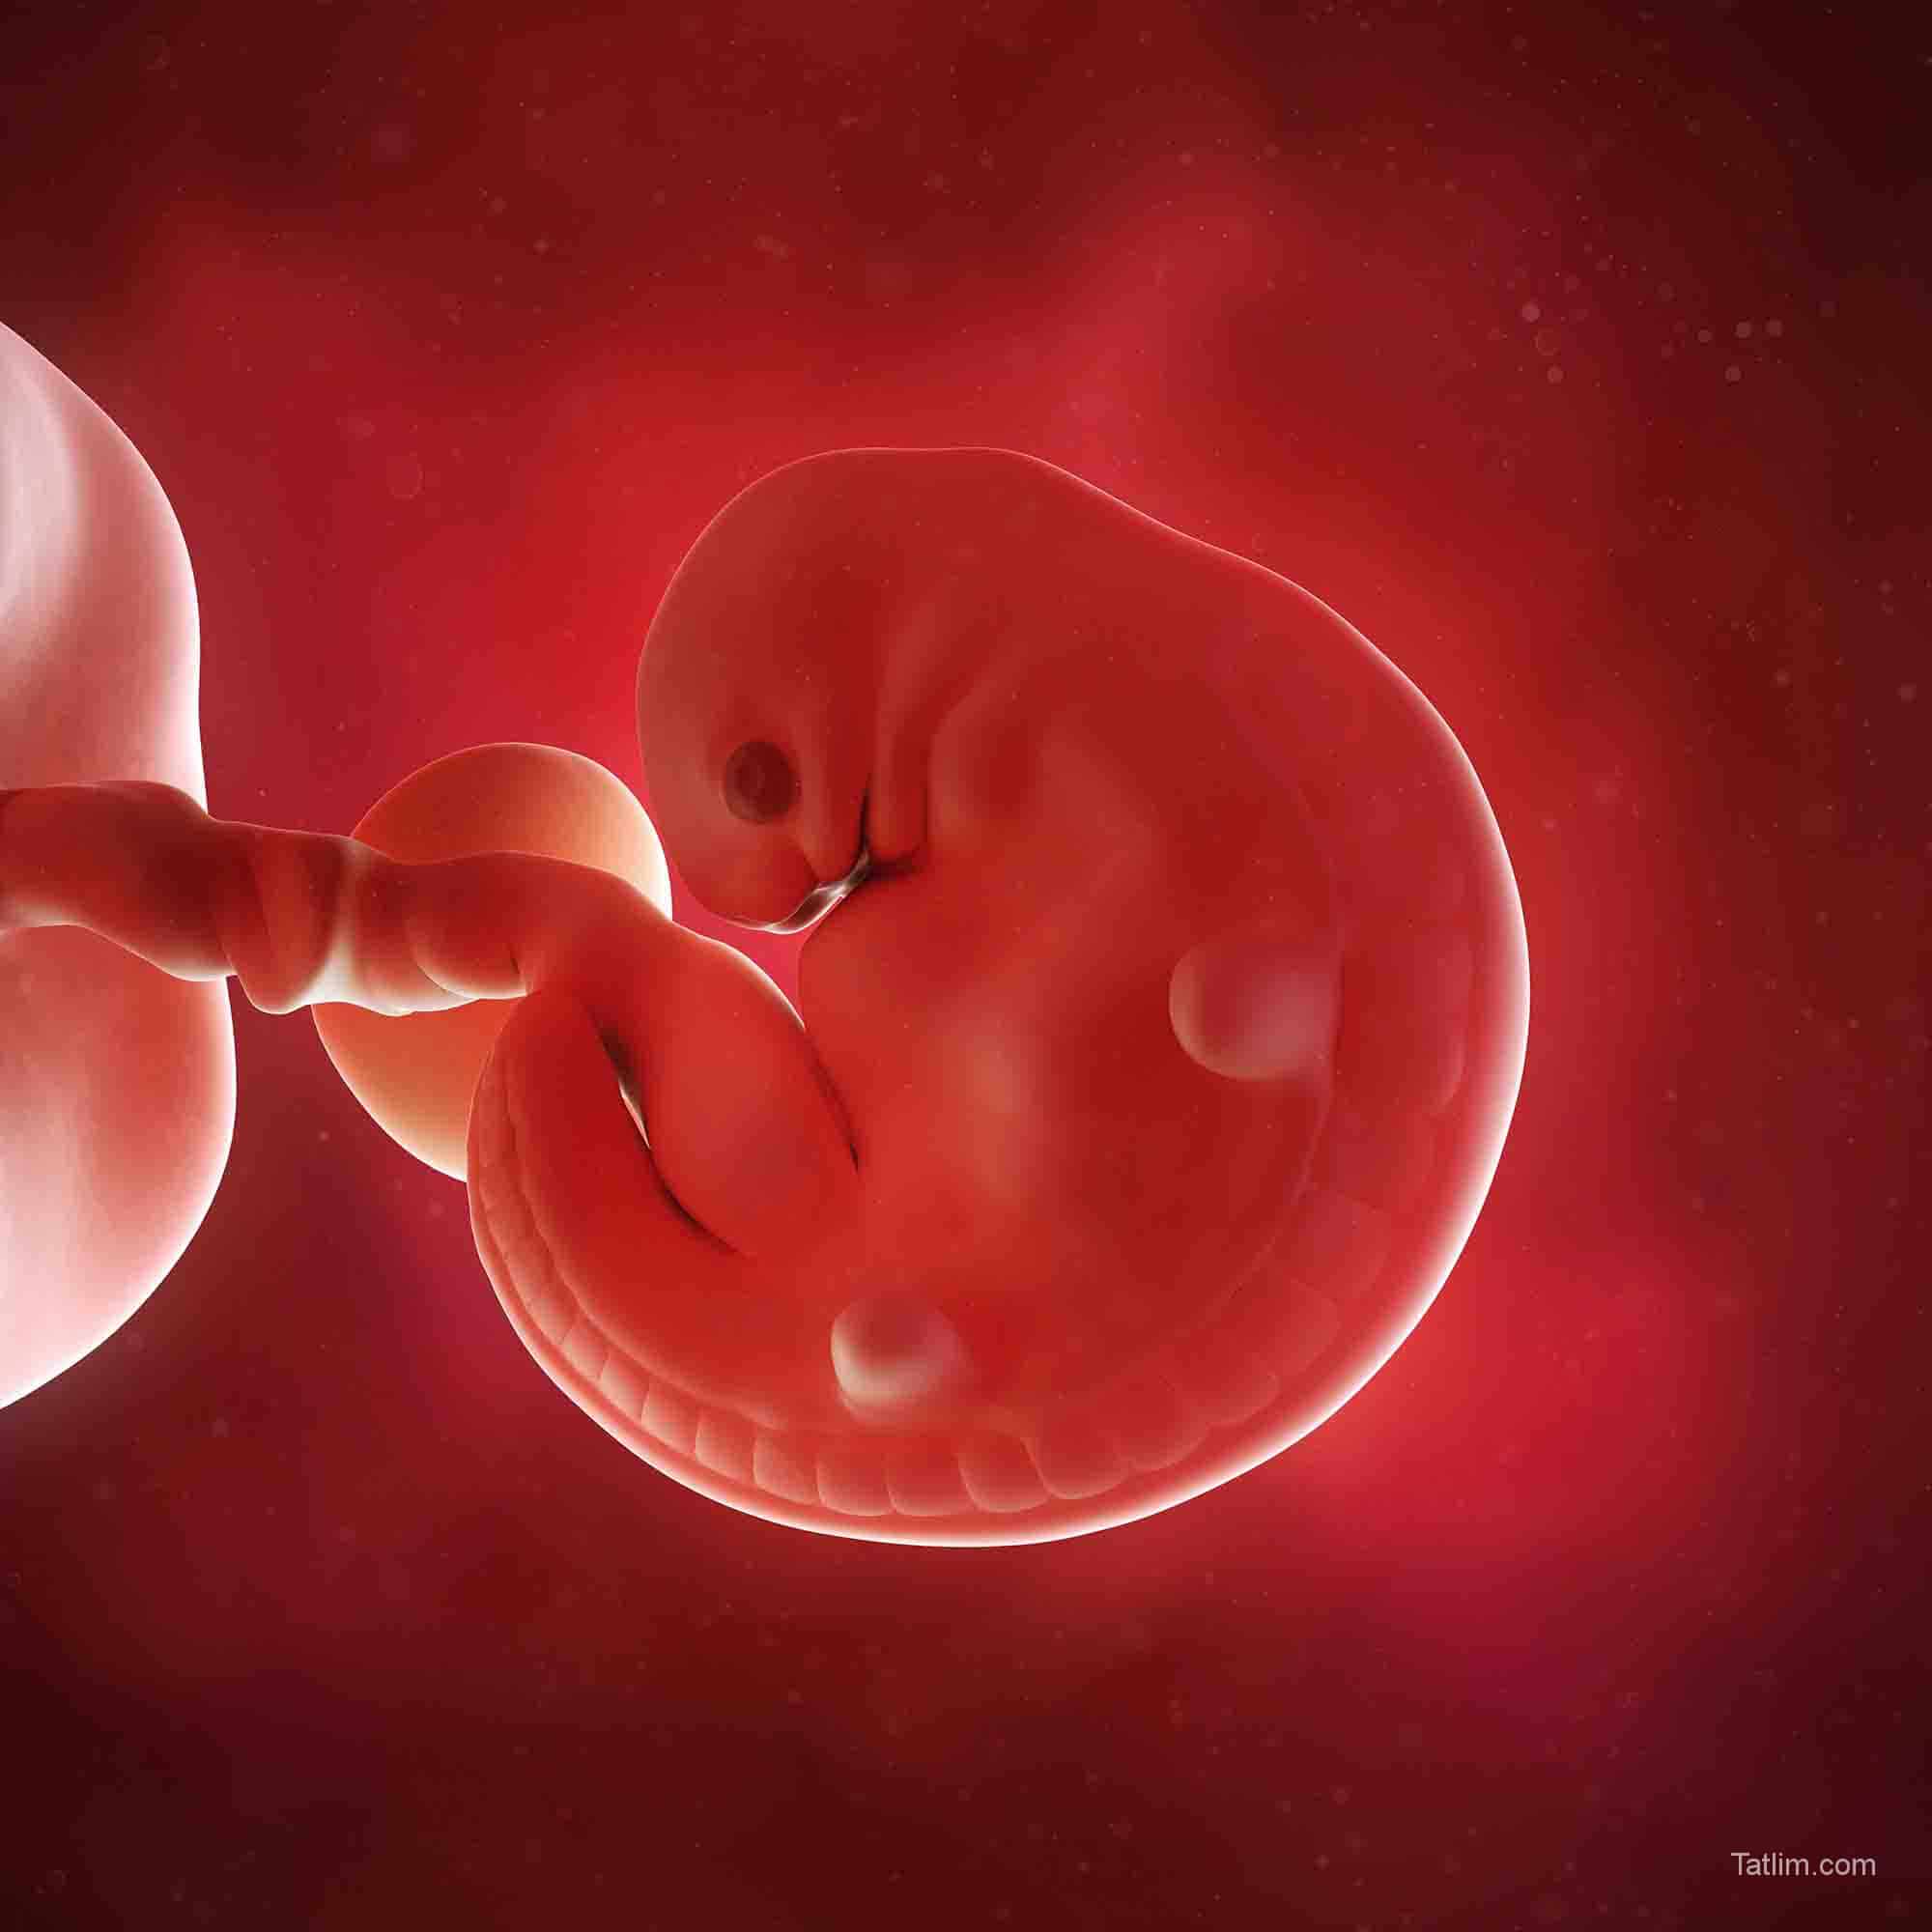

6 Haftalık Bebek Gelişimi From Pinterest

6 Haftalık Bebek Gelişimi From Pinterest

Hafta bebek gelişimi, 6 haftalık bebek görünümü, 6 haftalık bebek nasıl olur, 6 haftalık hamilelik, gebelikte 6 hafta bebeğin boyu ve kilosu, 6. Hamilelik dönemlerinde 1 aylık ultrason görüntüsü ayrı bir yer eden konudur. İşte bu nedenden dolayıdır ki, 4 haftadan önce bir hamilelik söz konusu değildir ve yine bu nedene bağlı olarak da 4 hafta öncesinde bebeğin görüntüsü de doğal olarak elde edilemez. Bebeğinizin cinsel organları hamilelik 5. Hamileliğin birinci ayında âdet gecikmesi yeni yeni olur. Amniyotik keseye dönüşecek olan amniyotik sıvı blastosit ismi.

hamilelikte5hafta Tatlım

Source:

Normal kiloda bir kadın hamilelik boyunca toplam 12.5 ila 17.5 arası kilo almalıdır. Hafta bebek gelişimi, 6 haftalık bebek görünümü, 6 haftalık bebek nasıl olur, 6 haftalık hamilelik, gebelikte 6 hafta bebeğin boyu ve kilosu, 6. Anne karnında ay ay bebek gelişmi.